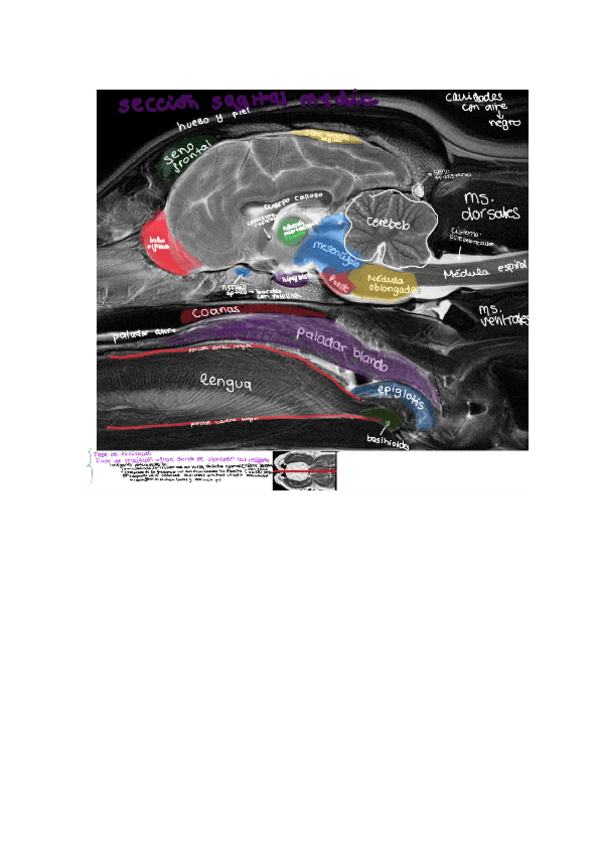

ANATOMIA-SECCIONAL-DE-LA-CABEZA-MEDIANTE-RESONANCIA-MAGNETICA-practica-7.pdf

He publicado nuevos apuntes de 1º Anatomía II: PRACTICA-7-RESONANCIA-MAGNETICA-DE-LA-CABEZA.pdf

He publicado nuevos apuntes de 1º Anatomía II: PRACTICA-7-RESONANCIA-MAGNETICA-DE-LA-CABEZA-VACIO.pdf